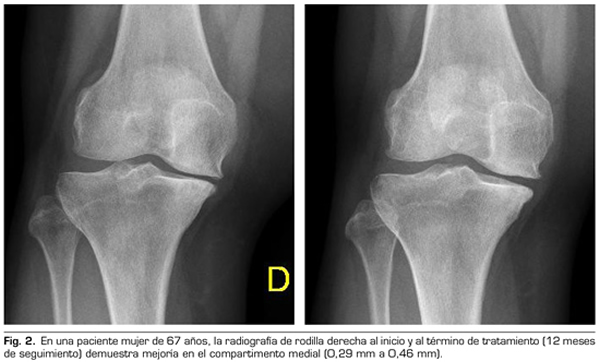

Con respecto a las variables radiológicas, al valorar a 53 de los 115 pacientes que cumplieron un año de seguimiento después del tratamiento con ozono, se observó que el compartimento interno aumento significativamente de 4,12 ± 1,41 mm a 4,4 ± 1,35 mm (p = 0,0008) y el compartimento externo aumentó de 6 ± 1,37 a 6,16 ± 1,4 mm (p = 0,0753) (Tabla II). Se presentan 2 casos clínicos como muestra del cambio radiológico en los compartimentos interno y externo (Figuras 2 y 3).

Para la evaluación radiográfica de la articulación tibiofemoral medial y lateral, se realizaron radiografías bilaterales anteroposteriores, con ambas piernas apoyadas y completamente extendidas, en carga según protocolo estandarizado (9). Todas las imágenes radiográficas se adquirieron digitalmente mediante un sistema de comunicación de archivo de imágenes (PACS). Se evaluó a 53 pacientes de los 115 que cumplieron un año de seguimiento tras la primera infiltración. Se midió la distancia femorotibial en la radiografía en los compartimentos medial y lateral en la distancia percibida como la más estrecha del espacio articular, y utilizando el programa de medición PACS. Todas las evaluaciones fueron llevadas a cabo por un solo autor, con el fin de reducir la variación interobservador, cuyo coeficiente de variación para medidas repetidas es 3-8 % (9,10).